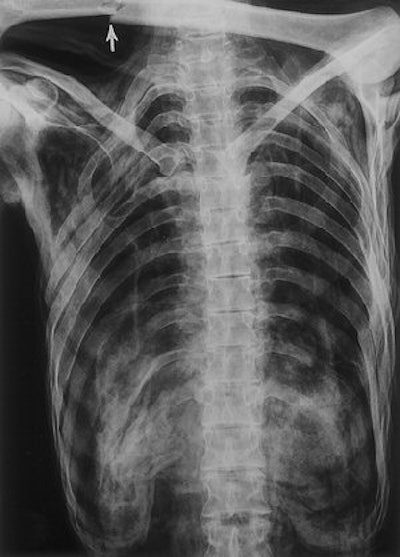

![]() |

| Frontal radiograph of the chest and upper abdomen (obtained on May 25, 1993) confirms the caudal rotation of the ribs and shows the folded soft tissues at the thoracolumbar junction. Only 11 rib-bearing thoracic vertebrae are present. The usual shadows of the heart, pulmonary vessels, and lungs are absent because of severe shrinkage of these organs. The fracture (arrow) of the left humerus was acquired during the recovery effort. |